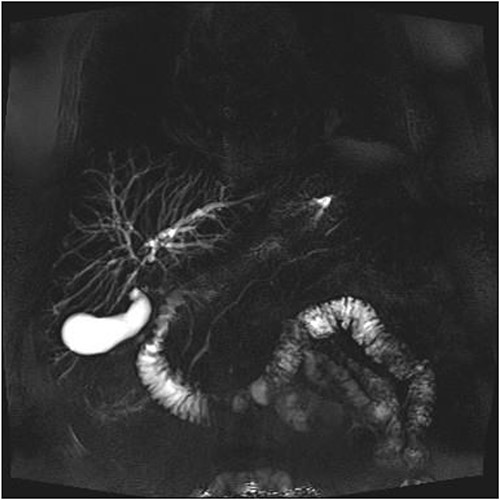

A man in his 70s presented to the emergency department with painless obstructive jaundice with dark urine and pale stools. The patient denied having any fever, nausea, vomiting, or weight loss. Liver function test progressively worsened during the admission peaking at a bilirubin of 287 umol/L (normal 2–20), alkaline phosphatase 694 U/L (normal 30–110), and alanine aminotransferase 160 U/L (normal < 40). Initial assessment on computed tomography and ultrasound raised concerns for primary pancreatic head neoplasm or cholangiocarcinoma (Fig. 1). He subsequently underwent magnetic resonance cholangiopancreatography (MRCP), which showed involvement of the entire common bile duct with no definite stricture or dilatation and no discrete pancreatic head mass (Fig. 2). Positron emission tomography showed abnormal uptake in the intrahepatic and extrahepatic bile ducts, focal uptake in the tail of the pancreas, and lymph nodes in the porta hepatis, retroperitoneum, and right iliac fossa (Fig. 3). Tumour markers revealed a carbohydrate antigen 19-9 (CA19-9) of 3286 kU/L (normal < 34).

CT scan showing thickening and enhancement of the entire extrahepatic common bile duct with intrahepatic duct dilatation.